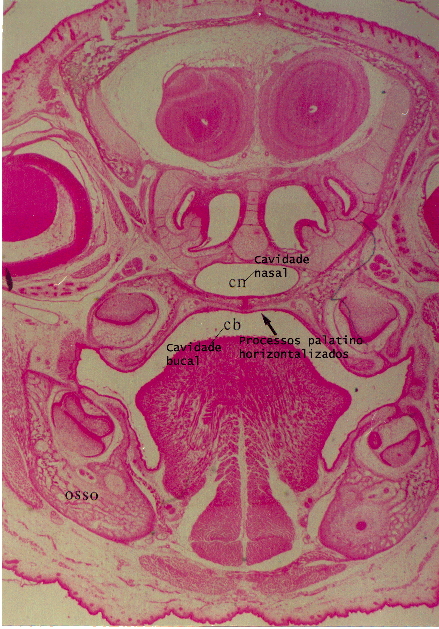

Desenvolvimento da face e odontogênese - Face and Tooth formation